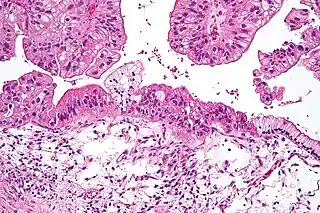

![]() Cistoadenocarcinoma mucinoso de ovario visto bajo el microscopio, tinición HE. | ||

El cistoadenocarcinoma es un tipo de cáncer o tumor maligno que se desarrolla a partir de tejido glandular y puede originarse en diferentes partes del organismo, principalmente ovario y páncreas, más raramente en apéndice, tiroides y glándulas salivares. El nombre proviene de que se forman pequeñas vesículas o quistes llenas de líquido y tapizadas por células tumorales. Existen dos variedades, el cistadenocarcinoma seroso en el que los quistes están llenos de un líquido seroso claro, y el cistadenocarcinoma mucinoso en el que la sustancia de los quistes es de consistencia gelatinosa. La variedad benigna de este tumor se denomina cistoadenoma. [1][2]